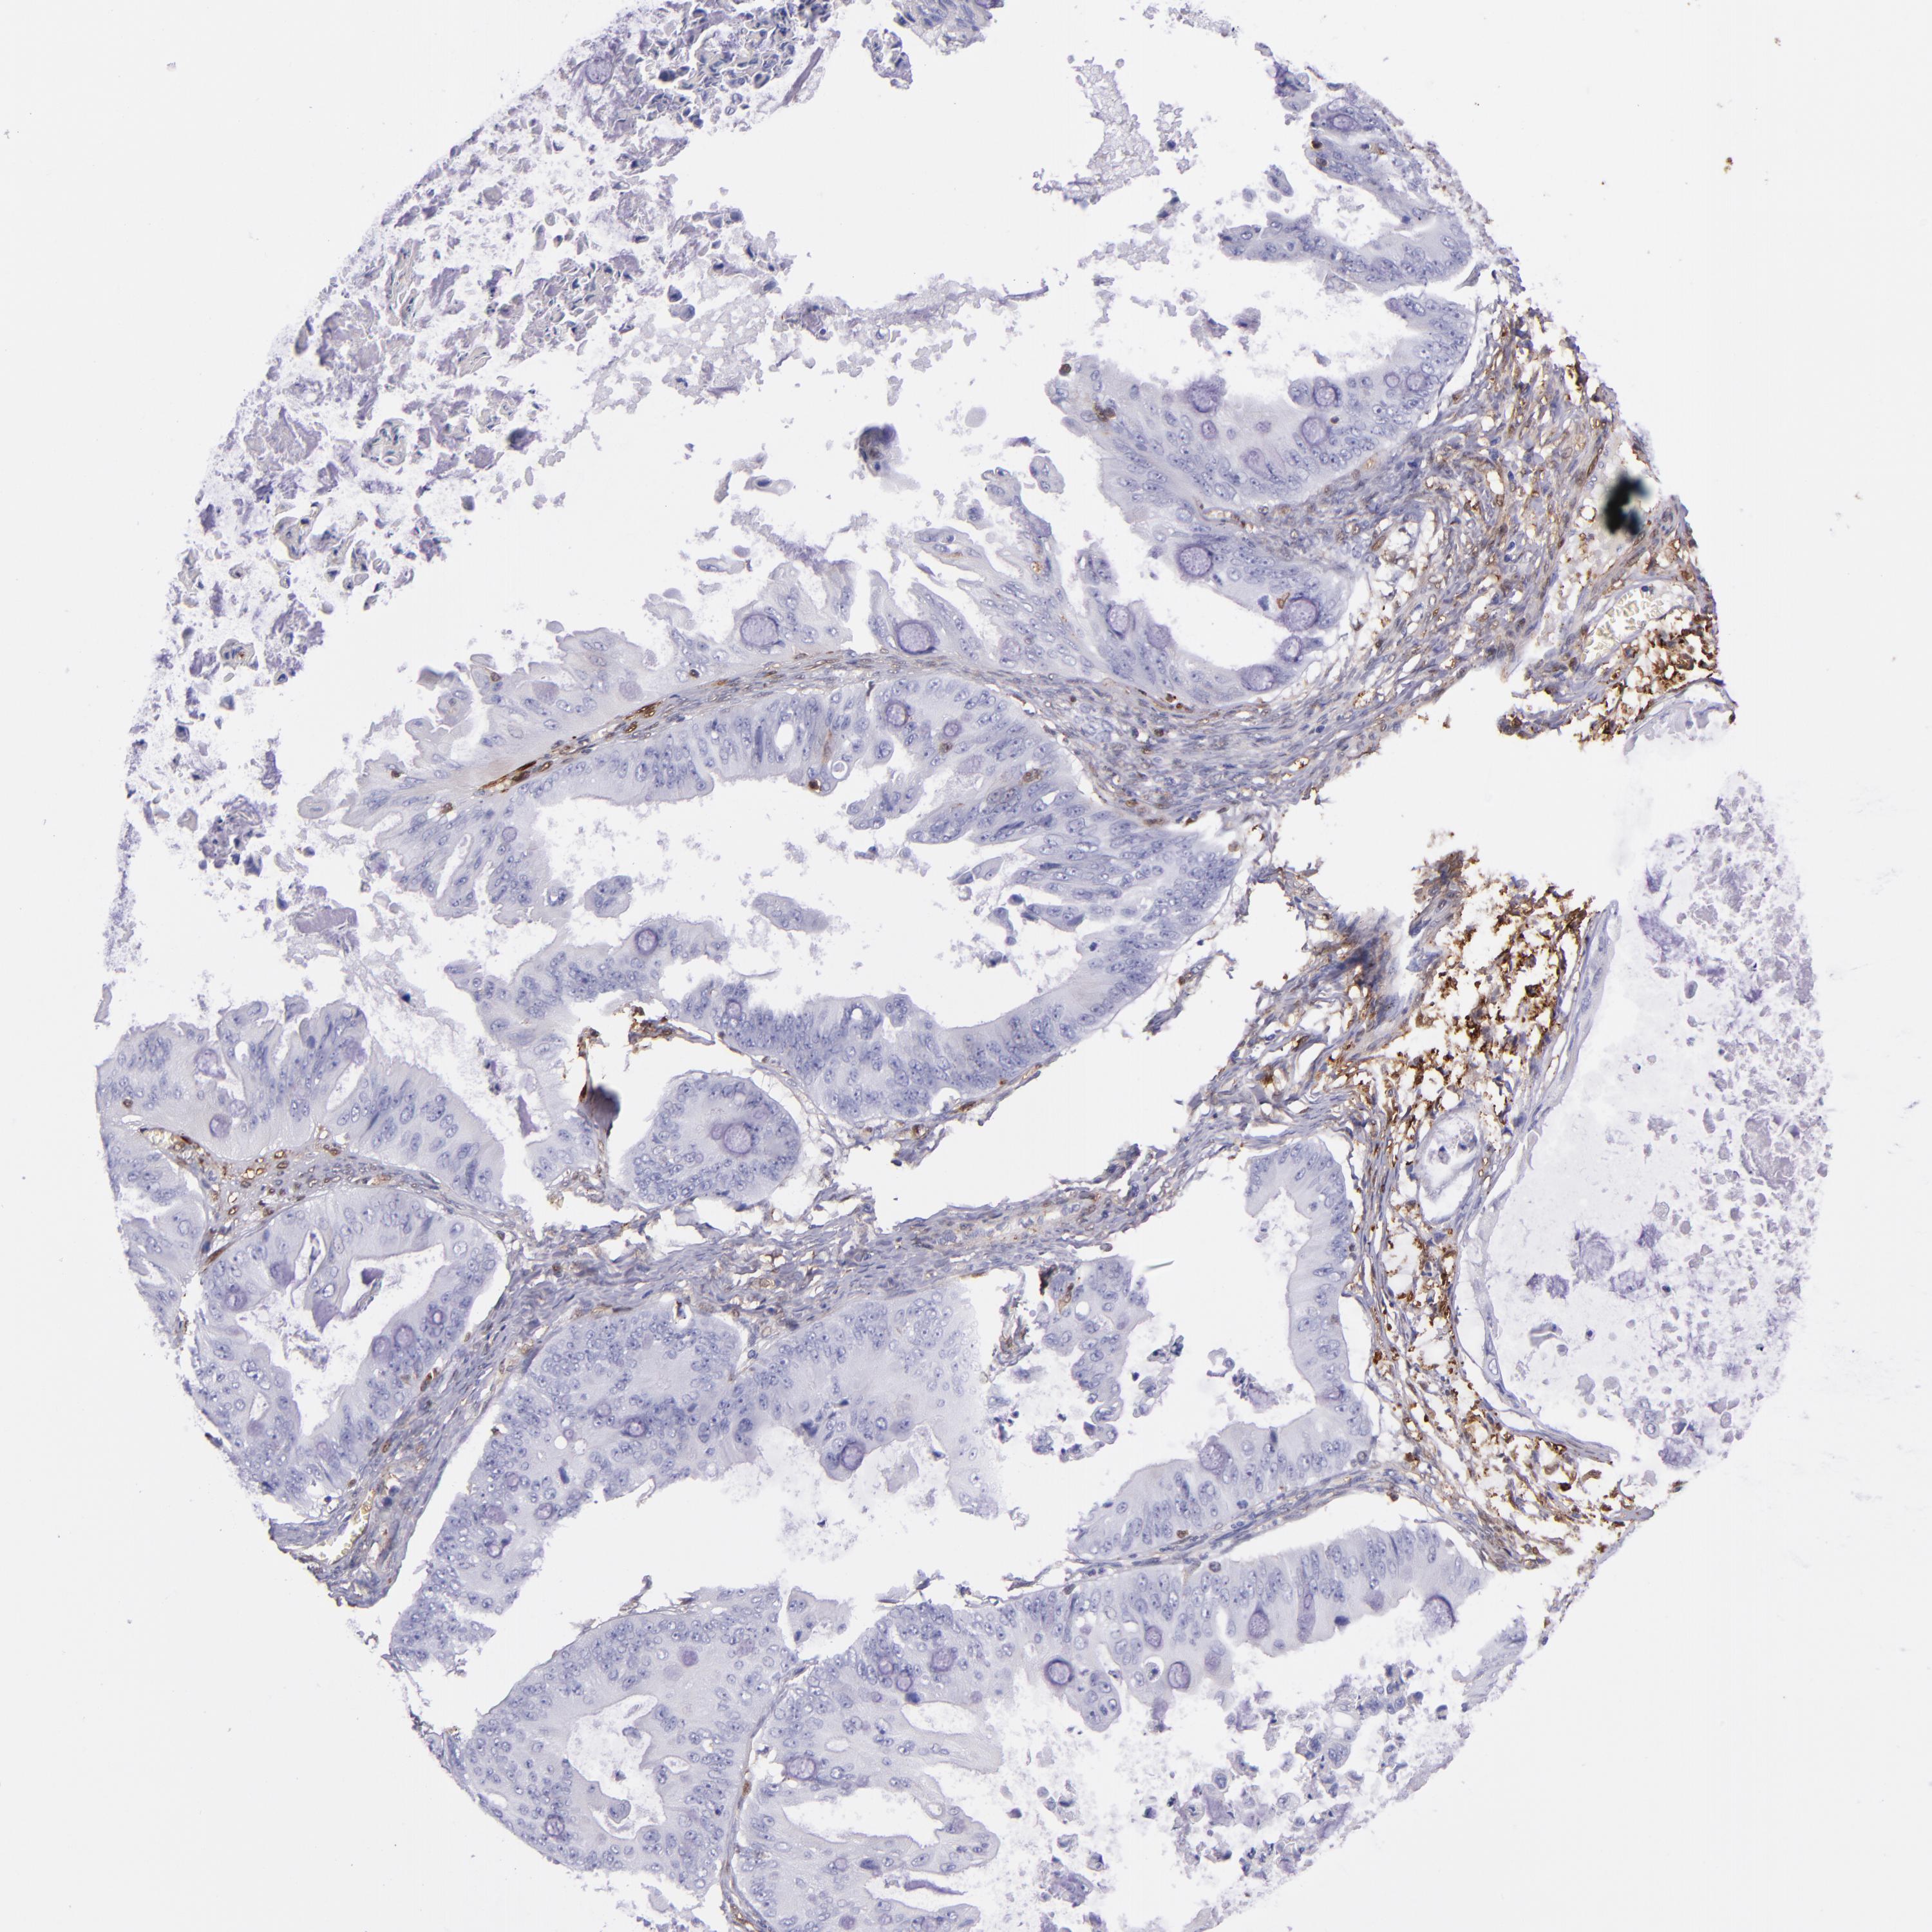

OVARIAN CANCER - Protein expressioni

A mouse-over function shows sample information and annotation data. Click on an image to view it in a full screen mode. Samples can be filtered based on level of antibody staining by selecting one or several of the following categories: high, medium, low and not detected. The assay and annotation is described here.

Note that samples used for immunohistochemistry by the Human Protein Atlas do not correspond to samples in the TCGA dataset.

Antibody stainingi

Antibody staining in the annotated cell types in the current human tissue is reported as not detected, low, medium, or high, based on conventional immunohistochemistry profiling in selected tissues. This score is based on the combination of the staining intensity and fraction of stained cells.

Each image is clickable and will lead to virtual microscopy that enables deeper exploration of all samples and also displays staining intensity scores, fraction scores and subcellular localization as well as patient and tissue information for each sample.

Antibody HPA000646

Antibody CAB002157

Staining

High

Medium

Low

Not detected

Intensity

Strong

Moderate

Weak

Negative

Quantity

>75%

75%-25%

<25%

None

Location

Nuclear

Cytoplasmic/membranous

Cytoplasmic/membranous,nuclear

Carcinoma, endometroid

Cystadenocarcinoma, serous, NOS

Cystadenocarcinoma, mucinous, NOS